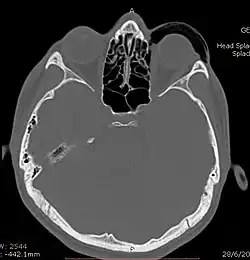

CT scan taken from the transverse plane demonstrating orbital emphysema.[39]